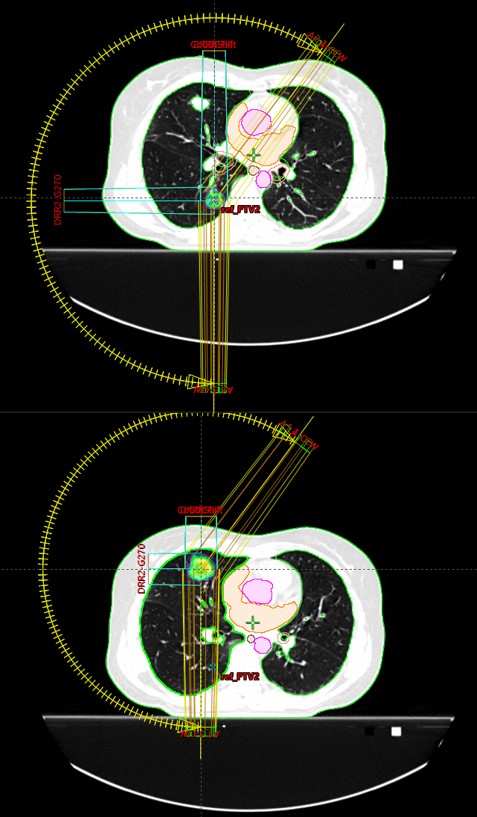

SABR meta pulmonum bilateralium (06/2017, 11/2019, 11/2020, 03/2021, 01/2022, 9/2023)

SABR meta pulm. et costae VIII l. sin. (5.4. – 6.4.2023.)